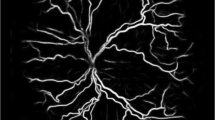

Retinopathy of prematurity (ROP) is a neovascular retinal disorder that occurs in low birth weight premature infants. It is a leading cause of childhood blindness in industrialized as well as developing nations [1]. In the USA, between 2000 and 2012, the incidence of ROP rose from 15% to 20% [2]. Elsewhere in the world, an increase in premature birth rates coupled with higher neonatal intensive care unit (NICU) admissions has also led to a substantial increase in the number of cases [3]. These increasing trends are largely hypothesized to be related to the advancement of neonatal care enabling higher survival rates among premature newborns worldwide [2], thus leading towards a growing ROP epidemic worldwide [3].

The goal of ROP screening is to recognize cases of potentially damaging ROP that necessitate treatment. ROP is classified according to the International Classification of Retinopathy of Prematurity (ICROP) that describes the disease by location (zone), stage, and extent [11]. Lower zone numbers and higher stage numbers indicate more severe ROP (Table 1). Plus disease refers to marked arteriolar tortuosity and venous engorgement of the posterior pole vasculature and signifies severe disease. Pre-plus disease refers to dilatation and tortuosity that are abnormal but less than plus disease. The first large treatment trial for ROP, the CRYO-ROP study, recommended treatment with cryotherapy when disease reached threshold severity. Threshold ROP in this study was defined as at least five contiguous or eight cumulative clock hours of stage 3 ROP in zones I and II, in the presence of plus disease (Table 2) [12]. Current treatment guidelines are based on the findings of the Early Treatment for Retinopathy of Prematurity (ETROP) trial published in 2003 [13]. Type 1 ROP refers to ROP that requires treatment and type 2 ROP refers to eyes that may be carefully monitored without treatment [13]. Eyes requiring treatment are those with any stage ROP in zone I with plus disease, stage 3 ROP in zone I without plus disease, and stage 2 or 3 ROP in zone II with plus disease [13]. Eyes that can be monitored are those with stage 1 or 2 ROP in zone I without plus disease and those with stage 3 ROP in zone II without plus disease.

The gold standard camera currently used is the RetCam family of cameras (Clarity Medical Systems, Pleasanton, CA, USA). This system is contact-based and uses a coupling agent between the camera lens and cornea. Wide-angle photography with a 130° field-of-view of the fundus is preferred. Recently, novel noncontact digital cameras and smartphone-based imaging systems were developed for imaging the pediatric retina [27,28,29,30,31]. An RDFI-TM system based on the Pictor noncontact camera has been shown to have high sensitivity and specificity for detecting pre-plus and plus disease, at levels comparable to RetCam-based RDFI [29].

The diagnostic ability of ophthalmologists grading images in an RDFI-TM system depends on their capacity to recognize clinical patterns based on retinal appearance and vascular architecture. In a similar fashion, computer-based image analysis (CBIA) systems of fundus images can generate a diagnostic output based on predetermined image characteristics [34,35,36]. In the past decade, systems like ROPTool, Vessel Map, Retinal Image multiScale Analysis (RISA), and Computer Assisted Image Analysis of the Retina (CAIAR) have emerged to help clinicians recognize plus disease [37]. These systems consisted of feature extraction-based systems that quantified vascular dilation and tortuosity into a value that had diagnostic agreement with the clinical diagnosis of ROP as established by multiple expert clinicians (standard reference) [38]. Although promising, the accuracy of these systems’ outputs alone was not sufficient for wide adoption at the bedside or within RDFI-TM systems.

More recently, models using artificial intelligence (AI) have been developed to recognize plus disease [38]. Table 4 provides a summary of major machine learning models developed for the detection of plus disease in ROP. Machine learning is a subtype of AI that can be applied to image analysis in RDFI-TM systems. Supervised machine learning describes algorithms that can apply what has been learned in the past to new data using labeled examples [39]. In 2015, Ataer-Cansizoglu et al. described the Imaging and Informatics in ROP (i-ROP) model that uses support vector machine (SVM), a type of supervised machine learning that was trained to classify images on the basis of manual tracing and segmentation of the retinal vessels as an input. The model had 95% accuracy (experts: 96%, 94%, and 92%) for classifying plus disease compared to reference standards as determined consensus of three expert ROP image graders and clinical examination.

In 2016, Worall et al. demonstrated a plus disease detection tool using deep learning by employing convolutional neural networks (CNNs) [40]. CNNs automatically extract various type of image features that might be indicative of disease, as learned from a training set of images [39]. Worrall et al. used real-world datasets from Canada (1459 images) and the UK (106 images) labeled in a binary fashion: plus vs. no plus disease. For the diagnosis of plus disease, the accuracy was 92%, the sensitivity 82.5%, and the specificity 98%. The authors concluded that the classifier demonstrated good agreement with the expert labelers but also highlighted the limitations associated with the use of human-dependent training sets, since significant discrepancies can be present between clinicians in regards to plus disease diagnosis [40].

With this in mind, Tan et al. trained a CNN model using almost 7000 fundus images labeled by a single clinician at a single institution. The model detected plus disease with 97% sensitivity and 98% negative predictive value. These results are highly promising but additional work is needed to determine its real-world applicability to account for inter-clinician variations in the diagnosis of plus disease [41]. In a different approach to improve the reliability of training sets, Brown et al. used a reference standard diagnosis (RSD). RSD is founded on consensus diagnosis from multiple image gradings as well as a clinical diagnosis [42]. The i-ROP DL model, built to detect plus disease, was trained with data labeled with an RSD [42]. This algorithm diagnosed plus disease with comparable accuracy to human experts: 93% sensitivity and 94% specificity for plus disease and 100% sensitivity and 94% specificity for pre-plus disease [42].